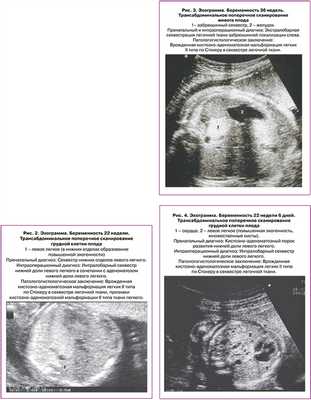

Морфологическая классификация КАМЛ предложенная J. Stocker, основана на размере кист и характере выстилающего их эпителия. Она одинаково удобна для описания как поражения собственно легочной ткани, так и секвестров легкого: I тип - большие кисты 2-10 см в диаметре, выстланные многослойным эпителием, II тип - кисты 0,5-2 см, выстланные цилиндрическим эпителием, III тип - микрокисты, менее 0,5 см в диаметре, выстланные кубическим эпителием. В последствии к этой оригинальной классификации было добавлено еще два типа 0 тип - солидная ткань и IV тип - одна большая киста. Эти два типа составляют всего 5% от всех кистозно-аденоматозных пороков развития легкого КАПРЛ [11]. В настоящее время существует мнение, что КАМЛ и ЛС нельзя всегда рассматривать как самостоятельные нозологические единицы. Морфологические исследования свидетельствуют о том, что около 50% КАМЛ и ЛС являются «гибридными формами», имеющими как признаки аномального строения ткани собственно легкого, так и характерные для секвестрации особенности кровоснабжения патологического участка [3, 11-14]. В целом происхождение, морфологические особенности и клинические данные этих заболеваний очень схожи, что позволяет объединить их в группу КАПРЛ (рис. 1-4).

Пренатальная диагностика аномалий легочной ткани в основном возможна с 20-21 недели беременности [1, 3, 8, 11]. При эхографии в грудной клетке плода определяется увеличение размеров и повышение эхогенности всего легкого или его части с наличием или отсутствием в нем кистозных включений. В подавляющем числе наблюдений изменениям подвергается одна из долей легкого и процесс имеет одностороннюю локализацию (более чем в 95% случаев) [1, 3, 8, 11]. В 26-28 недель беременности наблюдается пик роста легочной патологии [1, 8]. В дальнейшем, обычно после 32 недель, может происходить уменьшение размера или полное исчезновение внутриутробных эхографических признаков данной патологии [4, 6, 9, 12, 15-18].